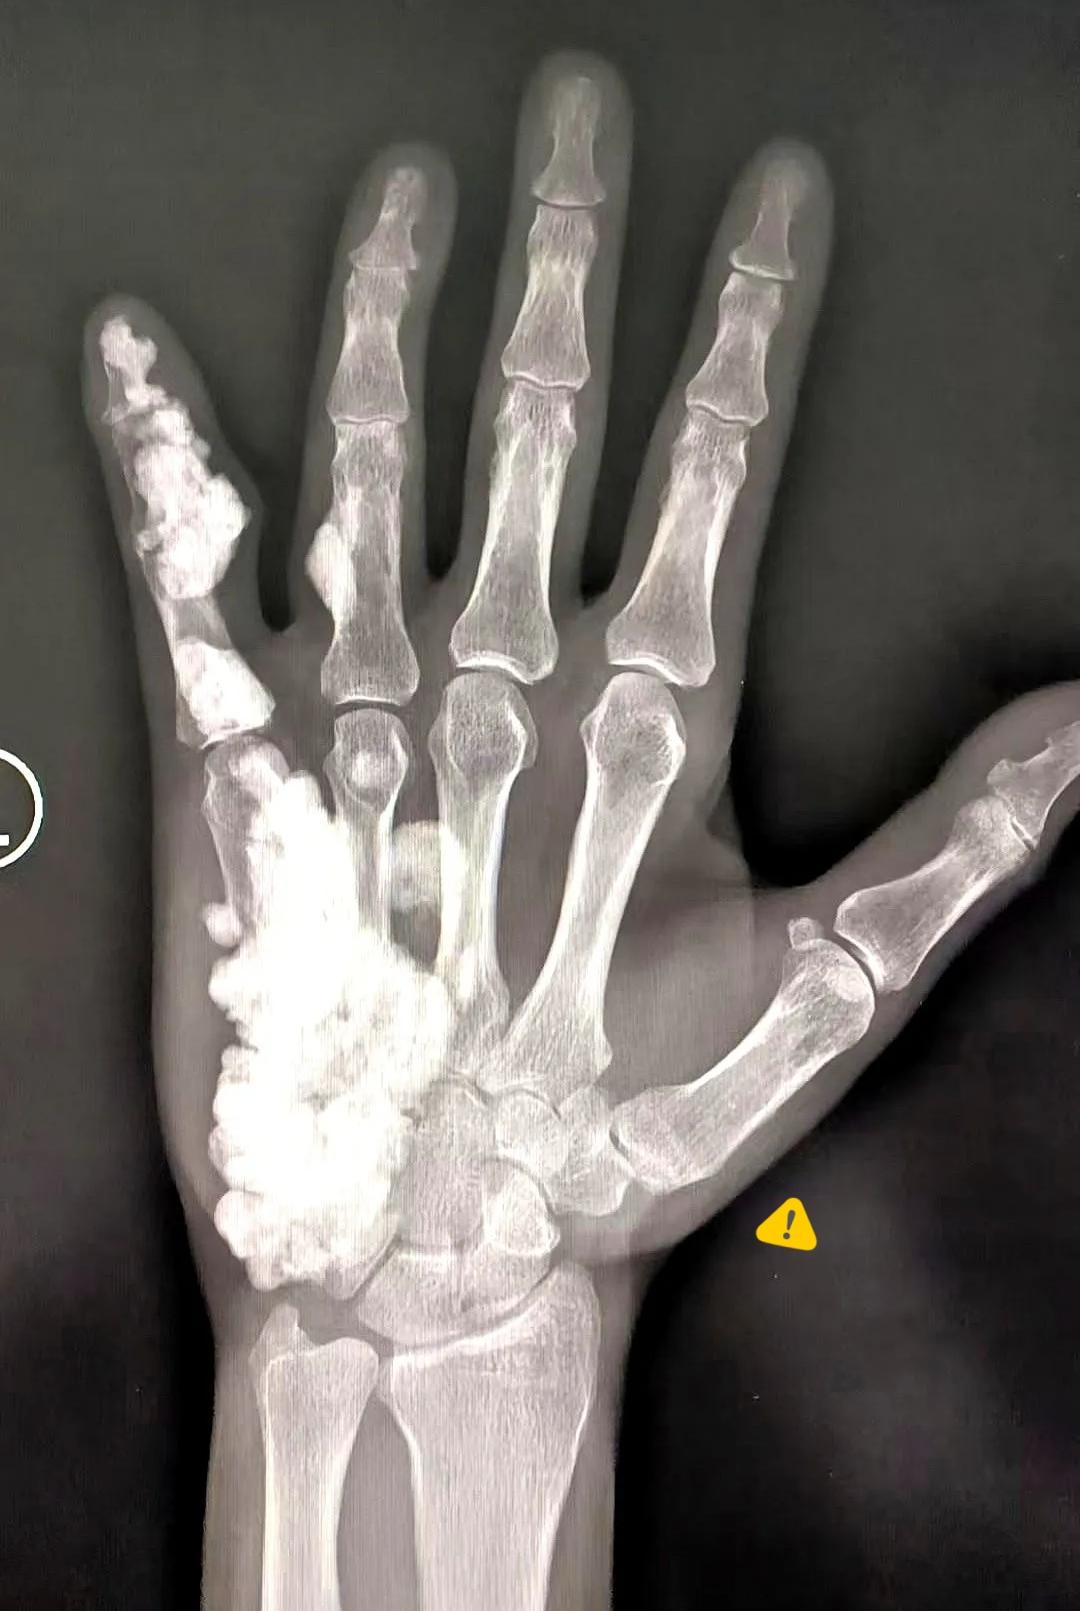

17岁,左手疼了整整10年。 拍了个片子,我人都看傻了。 这根本不像正常骨头,像蜡烛烧化后蜡油往下淌,瞬间冻住,层层叠叠凹凸不平,密度硬得像石头。专家围着看,说了象牙骨、骨皮质硬化这些专业名词,我心里只认三个字:蜡油骨。 从7岁疼到17岁,本该肆意奔跑的年纪,却被持续的疼痛困住,想想都心疼。可最让人松口气的是,这个看着无比吓人的病,居然是良性的,不恶变、不容易骨折,只是长得夸张了点。 很多时候生活就是这样,外表张牙舞爪,内核并没那么可怕。疼就治,影响生活就手术修整,看似跨不过的坎,认真面对就有出路。身体用最惊悚的样子提醒我们好好爱护自己,也教会我们淡定面对意外。 你有没有遇过看似吓人、其实没那么糟的事?

的确首先考虑蜡泪样骨病,但不足够典型。曾有幸先后受教于中国骨关节影像学泰斗曹来宾教授和他的女儿曹庆选教授,典型的片子也看了一些,印象最深的一个从髋关节开始,贴着一侧骨皮质,沿着股肯,胫骨,跨越关节一直到脚,真的犹就像蜡烛的烛泪一样。那些说骨癌(骨肉瘤)的,一没有软组织肿块,二无放射状骨针,三无骨膜反应,不支持。说痛风的,痛风是尿酸盐结晶,密度一般没有这么高,表现为骨质破坏为主。氟骨症与石骨症倒是也可以弥漫的骨质密度增高,但那个基本上是累及所有骨头的,骨头的外形变他不是那么明显。千问的判断还算靠谱

根据影像特征和博主描述,这并非痛风或骨癌。其骨骼增生形态似“蜡泪”,符合“蜡泪样骨病”特征。这是一种良性病变,不会恶变,与痛风的尿酸盐沉积或骨癌的恶性破坏在病理上有本质区别。博主也已确认诊断为良性。

博主17岁,左手疼痛10年,X光显示骨骼异常增生,形似“蜡油”。经诊断为良性病变,虽外观吓人但不恶变、不易骨折。博主感悟:外表张牙舞爪的事,内核未必可怕,认真面对就有出路。

根据医学资料,蜡油样骨病目前没有特效药能完全根治。治疗主要针对症状,如果疼痛或关节功能受影响,可通过手术切除病变骨质来改善。如果无明显症状,也可选择随访观察。博主提到的“良性”和“不恶变”是关键,祝早日康复~

根据目前的医学资料,蜡油样骨病尚无根治方法。治疗主要针对症状:疼痛可用药或理疗;若畸形或压迫神经严重影响生活,可手术。但手术有复发可能。博主的病是良性的,这一点确实值得庆幸。

根据博主描述的“蜡油骨”、“象牙骨”和“骨皮质硬化”等特征,这很可能是骨软骨瘤(Osteochondroma),一种良性骨肿瘤。其特点是骨表面有“滴蜡样”的骨质增生,与X光片形态相符。博主提到的“良性、不恶变”也符合该病特点,但具体诊断需遵医嘱。